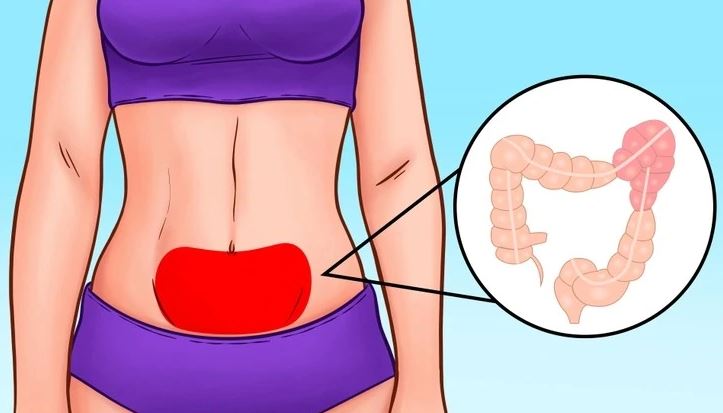

#4 Zmeny v črevnom mikrobióme

Počas dlhších vesmírnych misií dochádza u astronautov k výrazným zmenám v ich črevnom mikrobióme. Rovnováha baktérií v tráviacom systéme sa mení, čo môže ovplyvniť trávenie, vstrebávanie živín, imunitné funkcie a dokonca aj náladu. NASA naďalej skúma, ako udržať zdravý mikrobióm vo vesmírnom prostredí, najmä pri dlhodobých misiách na Mars alebo Mesiac.